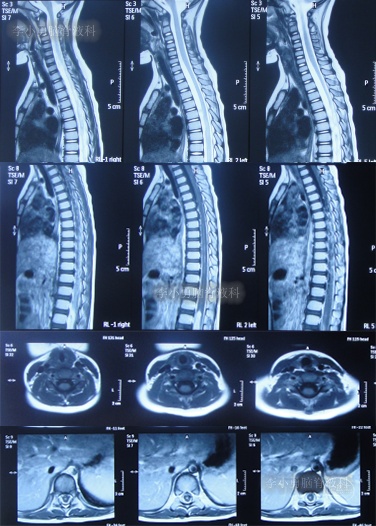

在第2家医院治疗13天即2022年5月24日,患儿仍间断高热,在医生建议下当天转至上级的第3家医院山东省某省级三甲医院,查脊髓核磁(图-2)后行腰椎穿刺有脓液吸出,给予腰大池置管术,但未见脑脊液流出,给予消炎、营养脑神经治疗。

图-2:2022年5月24日脊髓核磁